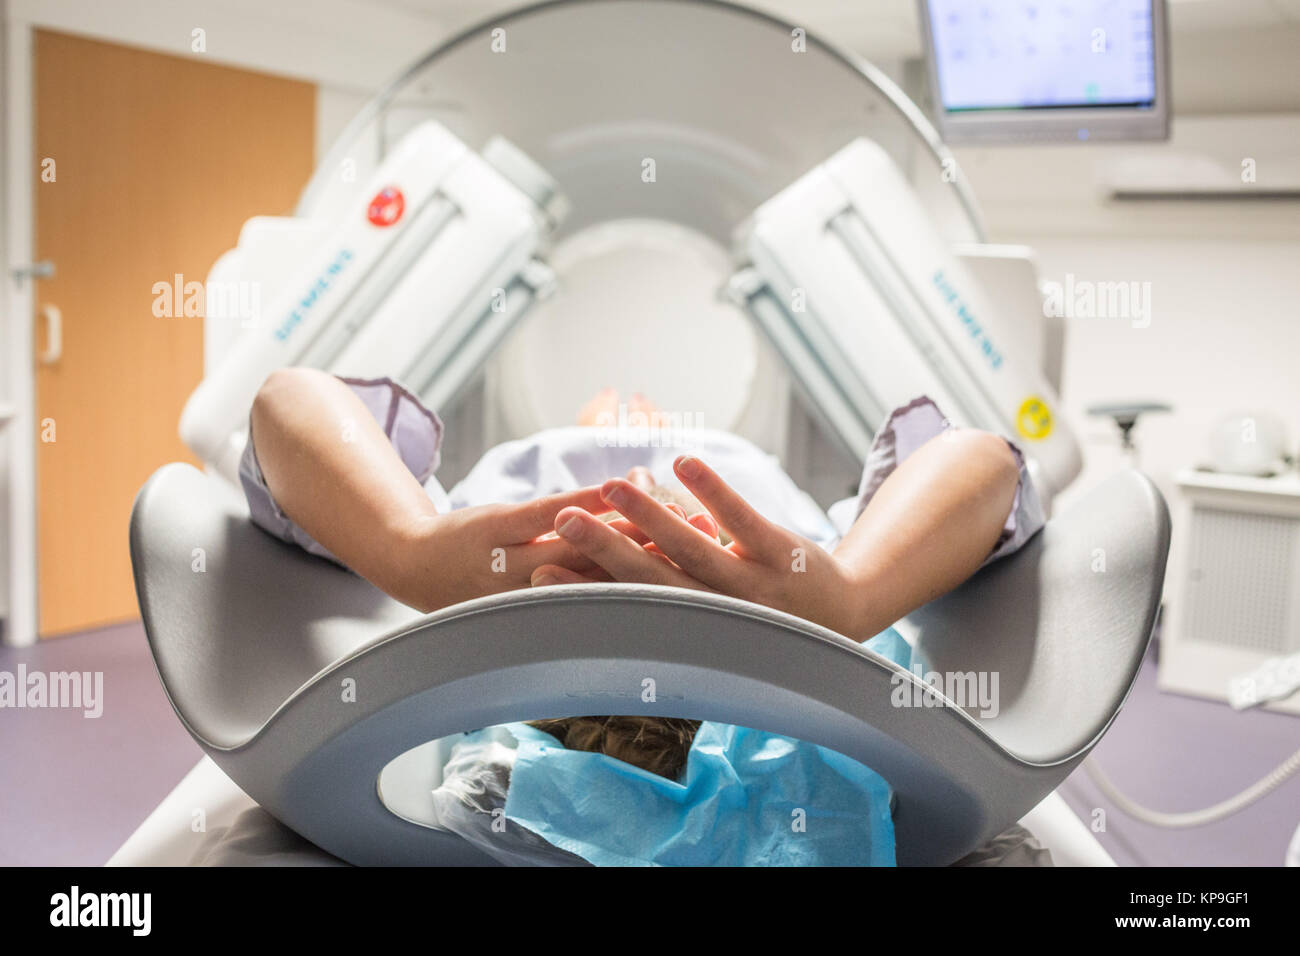

RMKP9GEB–À l'aide d'une scintigraphie couplée à un scanner, l'installation du patient par des techniciens en radiologie, Hôpital d'Angoulême, France.

RMKP9GG2–À l'aide d'une scintigraphie couplée à un scanner, l'installation du patient par des techniciens en radiologie, Hôpital d'Angoulême, France.

RMKP9GE2–À l'aide d'une scintigraphie couplée à un scanner, l'installation du patient par des techniciens en radiologie, Hôpital d'Angoulême, France.

RMKP9GFM–À l'aide d'une scintigraphie couplée à un scanner, l'installation du patient par des techniciens en radiologie, Hôpital d'Angoulême, France.

RMR59XBW–À l'aide d'une scintigraphie couplée à un scanner, l'installation du patient par des techniciens en radiologie, Hôpital d'Angoulême, France.

RMR59XCE–À l'aide d'une scintigraphie couplée à un scanner, l'installation du patient par des techniciens en radiologie, Hôpital d'Angoulême, France.

RMR59XCF–À l'aide d'une scintigraphie couplée à un scanner, l'installation du patient par des techniciens en radiologie, Hôpital d'Angoulême, France.